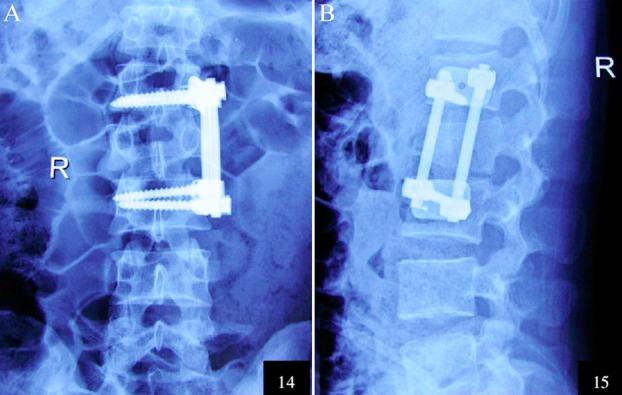

A total of 120 patients with TSF and SNI were selected and divided into a treatment group and a control group that were then treated by anterior decompression and posterior decompression respectively. The preoperative and postoperative motor scores, tactile scores, heights of injured vertebral body and Cobb's angles, as well as surgical times and intraoperative blood losses were recorded and compared.

Before surgeries, the motor score, tactile score, height of injured vertebral body and Cobb's angle of the treatment group were similar to those of the control group (P>0.05). After surgeries, the values of the treatment group were significantly different from those of the control group (P<0.05). The two groups also had significantly different intraoperative blood losses and surgical times (P<0.05).

Compared with posterior decompression, anterior decompression improved spinal cord function better and relived spinal cord compression more effectively with a more reasonable mechanics of internal fixation. Although this protocol caused more blood loss, the overall therapeutic effects were more satisfactory.